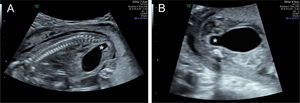

El diagnóstico diferencial de DTU depende en gran medida de la localización y del grado de dilatación dentro del tracto urinario. La hidronefrosis sin hidrouréter puede indicar una obstrucción de la unión pieloureteral (UPU) (fig. 4), mientras que la dilatación de la pelvis renal con hidrouréter sugiere más probablemente un reflujo vesicoureteral (RVU) o una obstrucción de la unión vesicoureteral (fig. 5). Además, una hidronefrosis severa puede, en ocasiones, simular RDMQ; por lo tanto, este último debe incluirse en el diagnóstico diferencial. Dado que un sistema colector renal duplicado puede asociarse con hidronefrosis en una o ambas porciones, se recomienda una evaluación detallada del aspecto renal y la búsqueda de un ureterocele en la vejiga. La dilatación de todo el sistema (riñón, uréter y vejiga) indica una obstrucción congénita del tracto urinario inferior (fig. 6), que puede tener diversas etiologías, como válvulas de uretra posterior (en fetos masculinos), atresia uretral o malformaciones cloacales (en fetos femeninos)19. Con excepción de la pielectasia transitoria, siempre se ofrece evaluación genética prenatal ante la sospecha de DTU fetal.

Hidronefrosis sin hidrouréter del riñón izquierdo alrededor de las 20semanas de edad gestacional. El riñón superior (izquierdo) muestra dilatación pélvica y caliectasia, mientras que el riñón inferior (derecho) presenta un aspecto normal. Imagen ecográfica del Centro Médico de la Universidad Erasmus.

Obstrucción del tracto urinario inferior alrededor de las 23 semanas de edad gestacional. Obsérvese la hidronefrosis bilateral, más prominente en uno de los dos riñones. La vejiga también está agrandada (no visible en esta imagen). Imagen ecográfica del Centro Médico de la Universidad Erasmus.